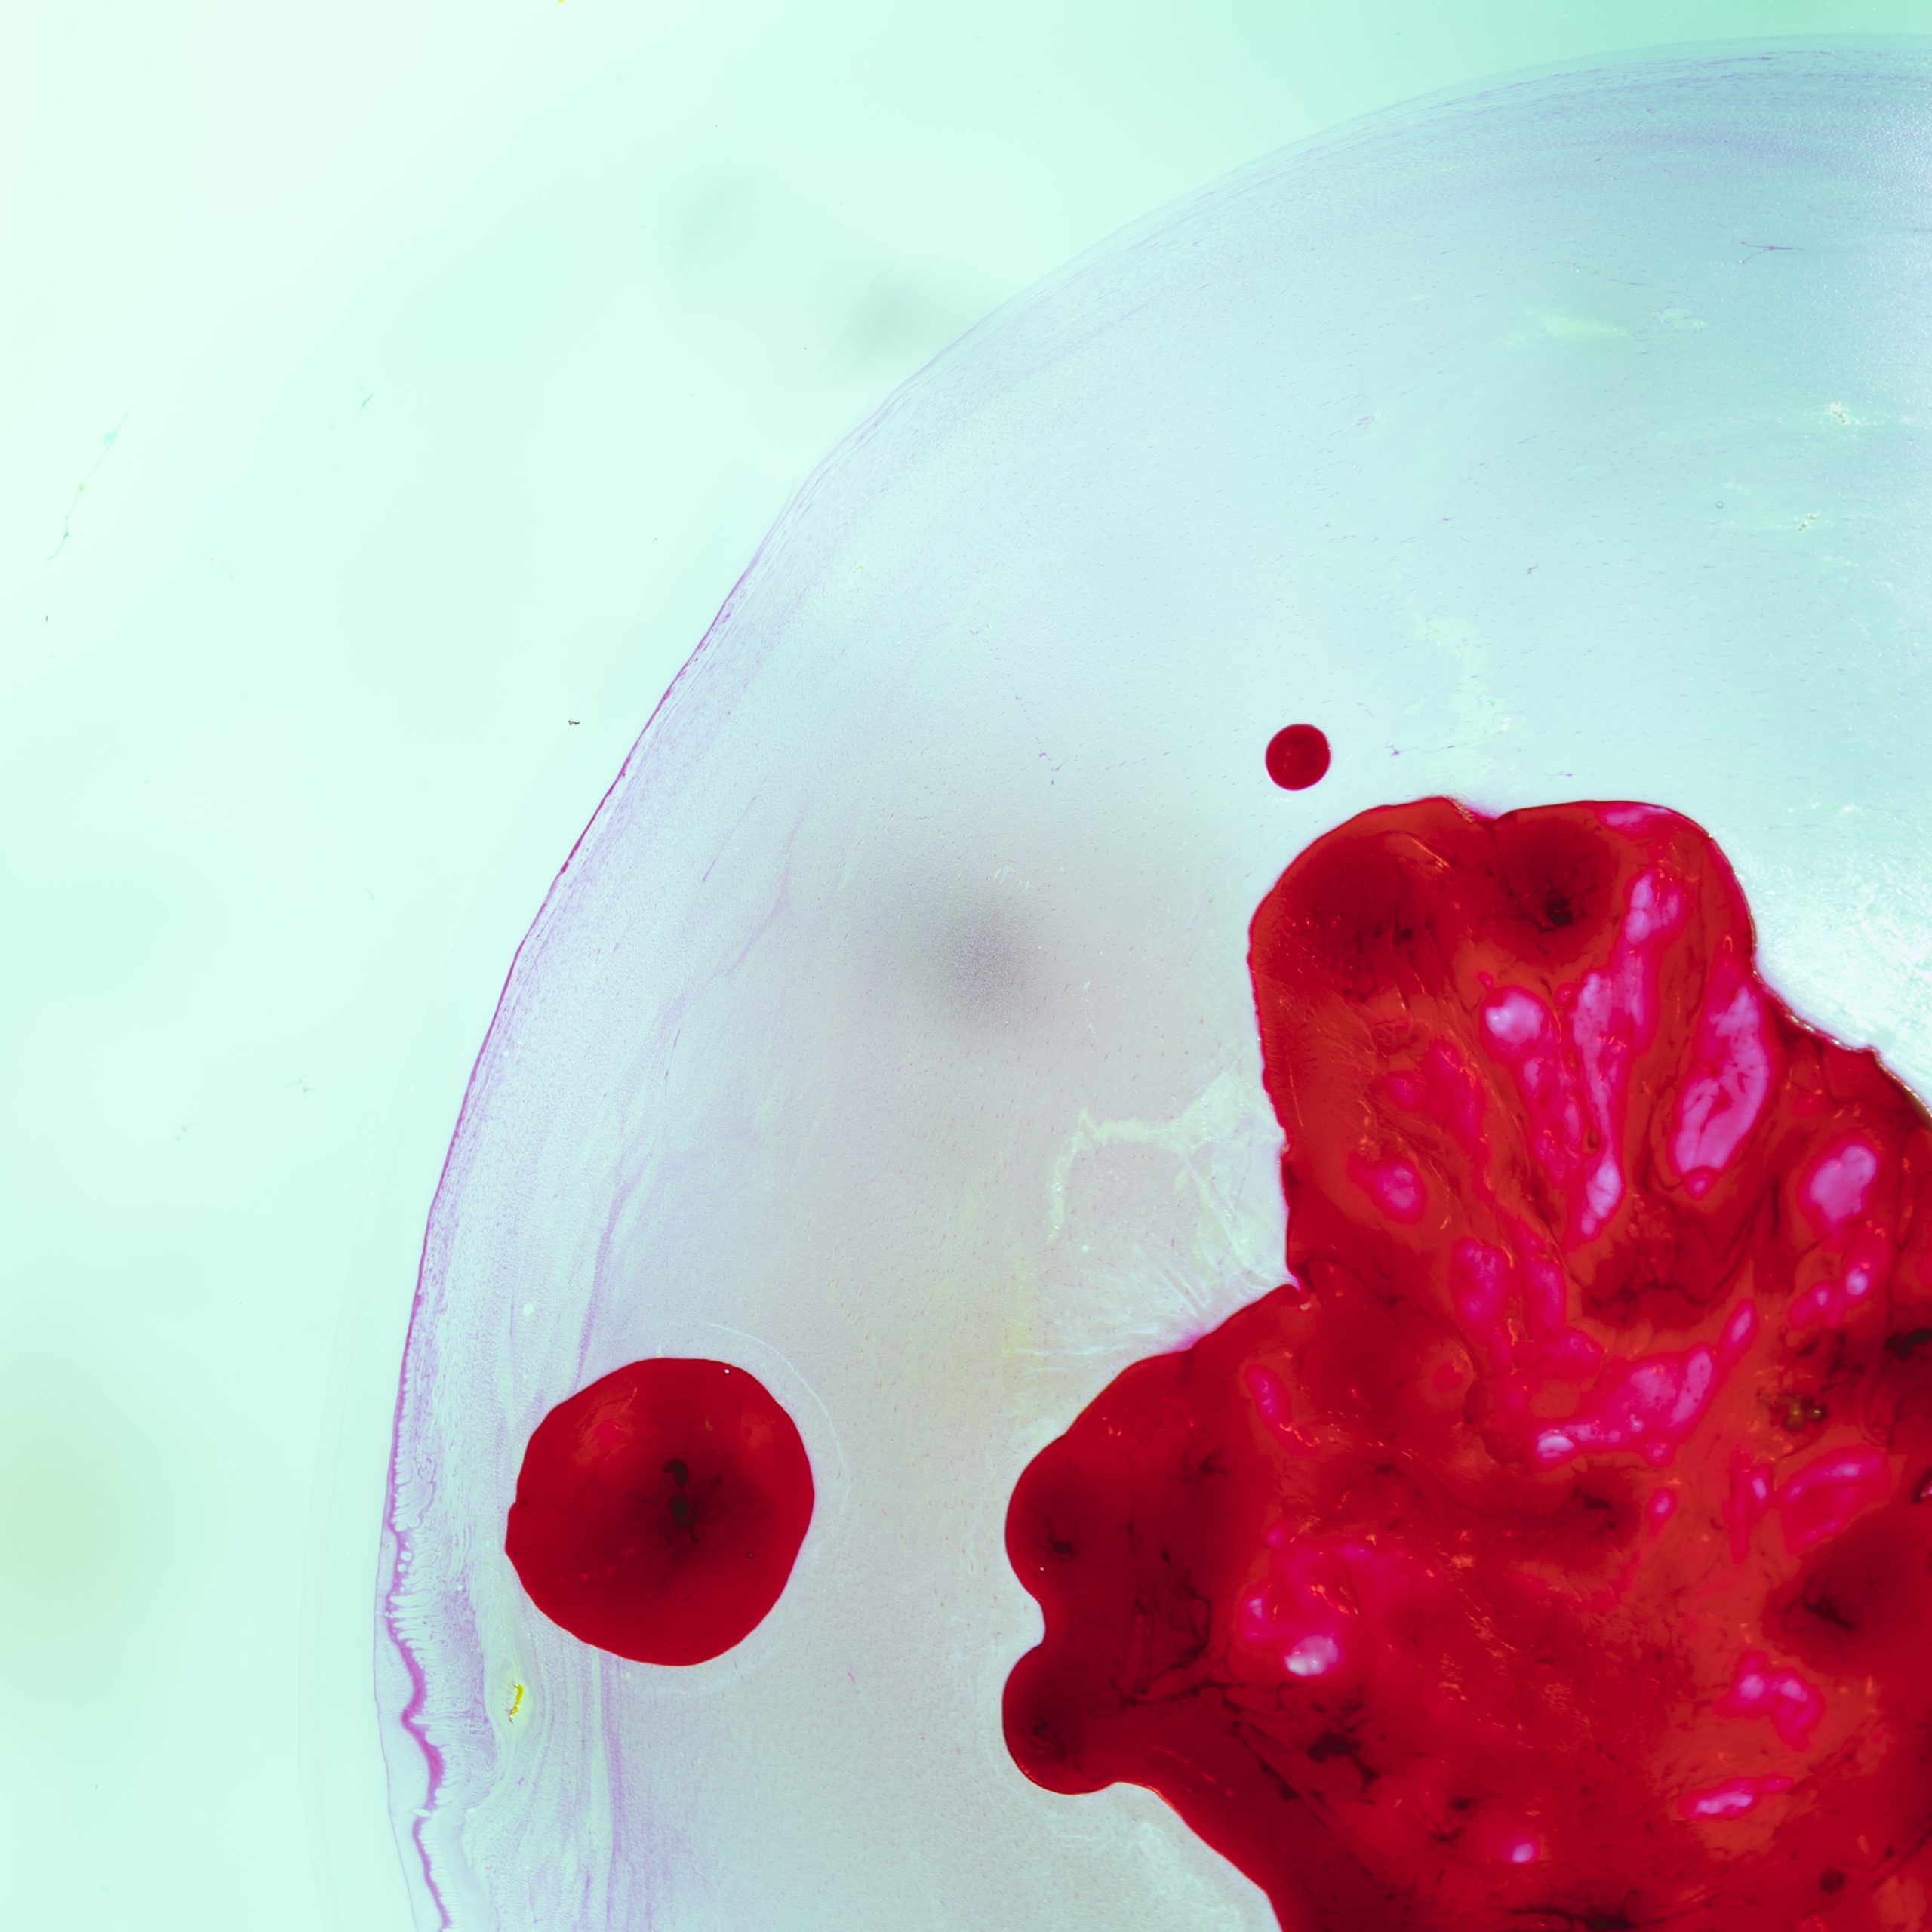

Hepatoblastoma usually shows up as a heterogeneous mass with variable echogenicity on ultrasound. This means the tumor can have different looks because of its mix of parts. Ultrasound imaging often shows a big mass that might be clear or spread out.

• A mix of echoes is common, showing the tumor’s varied makeup.

• Calcifications in the tumor are a big sign, found in many cases.

• Doppler ultrasound can check the tumor’s blood flow, giving more info.